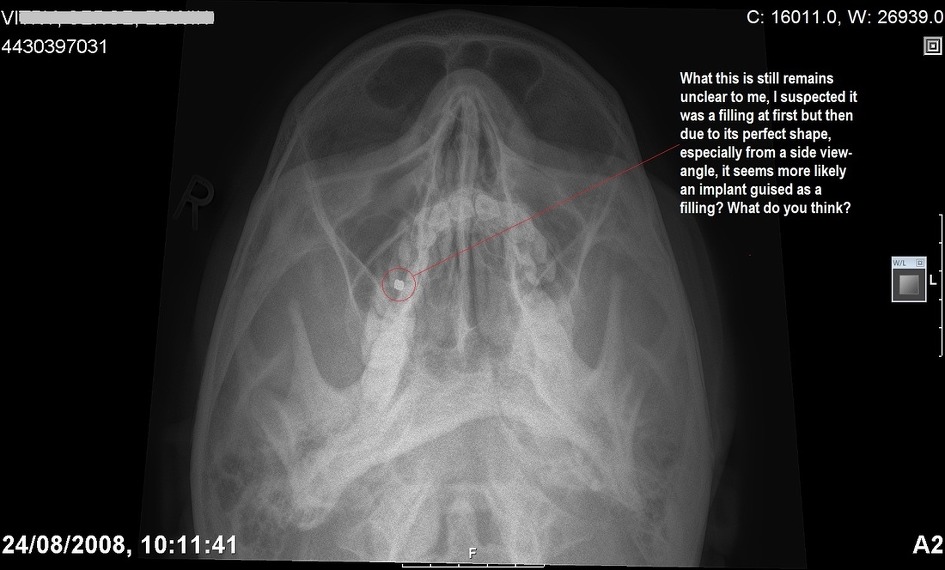

4. 마인드컨트롤 전자파 무기 피해자(TI: TARGETED INDIVIDUALS )들의 신체에 삽입된 칩

저도 뉴욕에 삽니다. 저의 동의없이 저도 TI 인대요..트라우마 기반 mindcontrol 실험대상자입니다. 2008년이래로 제 아들이 전기고문생체실험대상이 되었고, 2008년 이전에는 제 딸이 정신이상으로 정신과적 증상을 가지고 있습니다. 하루종일 기민증과 피곤함을 호소하고요. 저도 왼쪽팔이 마비가 오고, 이유없는 치통과 통증 그리고 건망증을 가지고 있습니다. 치과에 가서 사진을 찍어보니 치아는 이상이 없고요 단지 민감증 이라고만 했습니다. 제 오른다리는 항상 저리고 뜨겁게 달아오르고 가렵고 통증이 동반되고요.

피부가 분홍으로 부풀어 오르고 줄무늬가 생겨납니다. 제가 여기에 증거사진을 가지고 왔는데요.(엑스레이사진을 들어올려보입니다.)

저는 미시건에서 온 레슬리 크로포드라고 합니다. 저는 Bio-technology에 대해서 말씀드리고자 합니다. 여기 제가 안과에서 진료받은 진단과 사진을 가지고 왔습니다.(사진을 보여줍니다.) 안과사진과 두뇌스캔사진을 보여줍니다. 그리고 악관절 임플란트사진을 역시 보여줍니다.